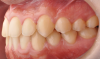

Fig 13. Dental views of the patient 3 years after surgical-orthodontic correction; right lateral view (Fig 13), frontal view (Fig 14), and left lateral view (Fig 15).

Figure 13